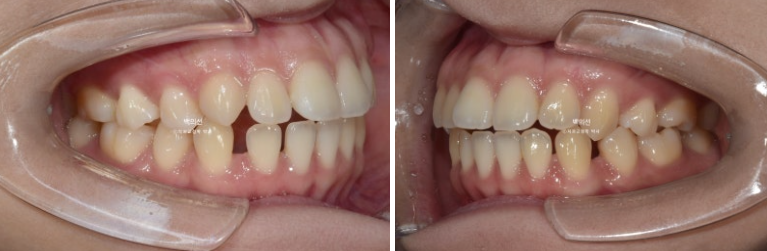

23.01

앞니 중심선이 다르고 아랫니에 듬성듬성 공간이 벌어져 있습니다.